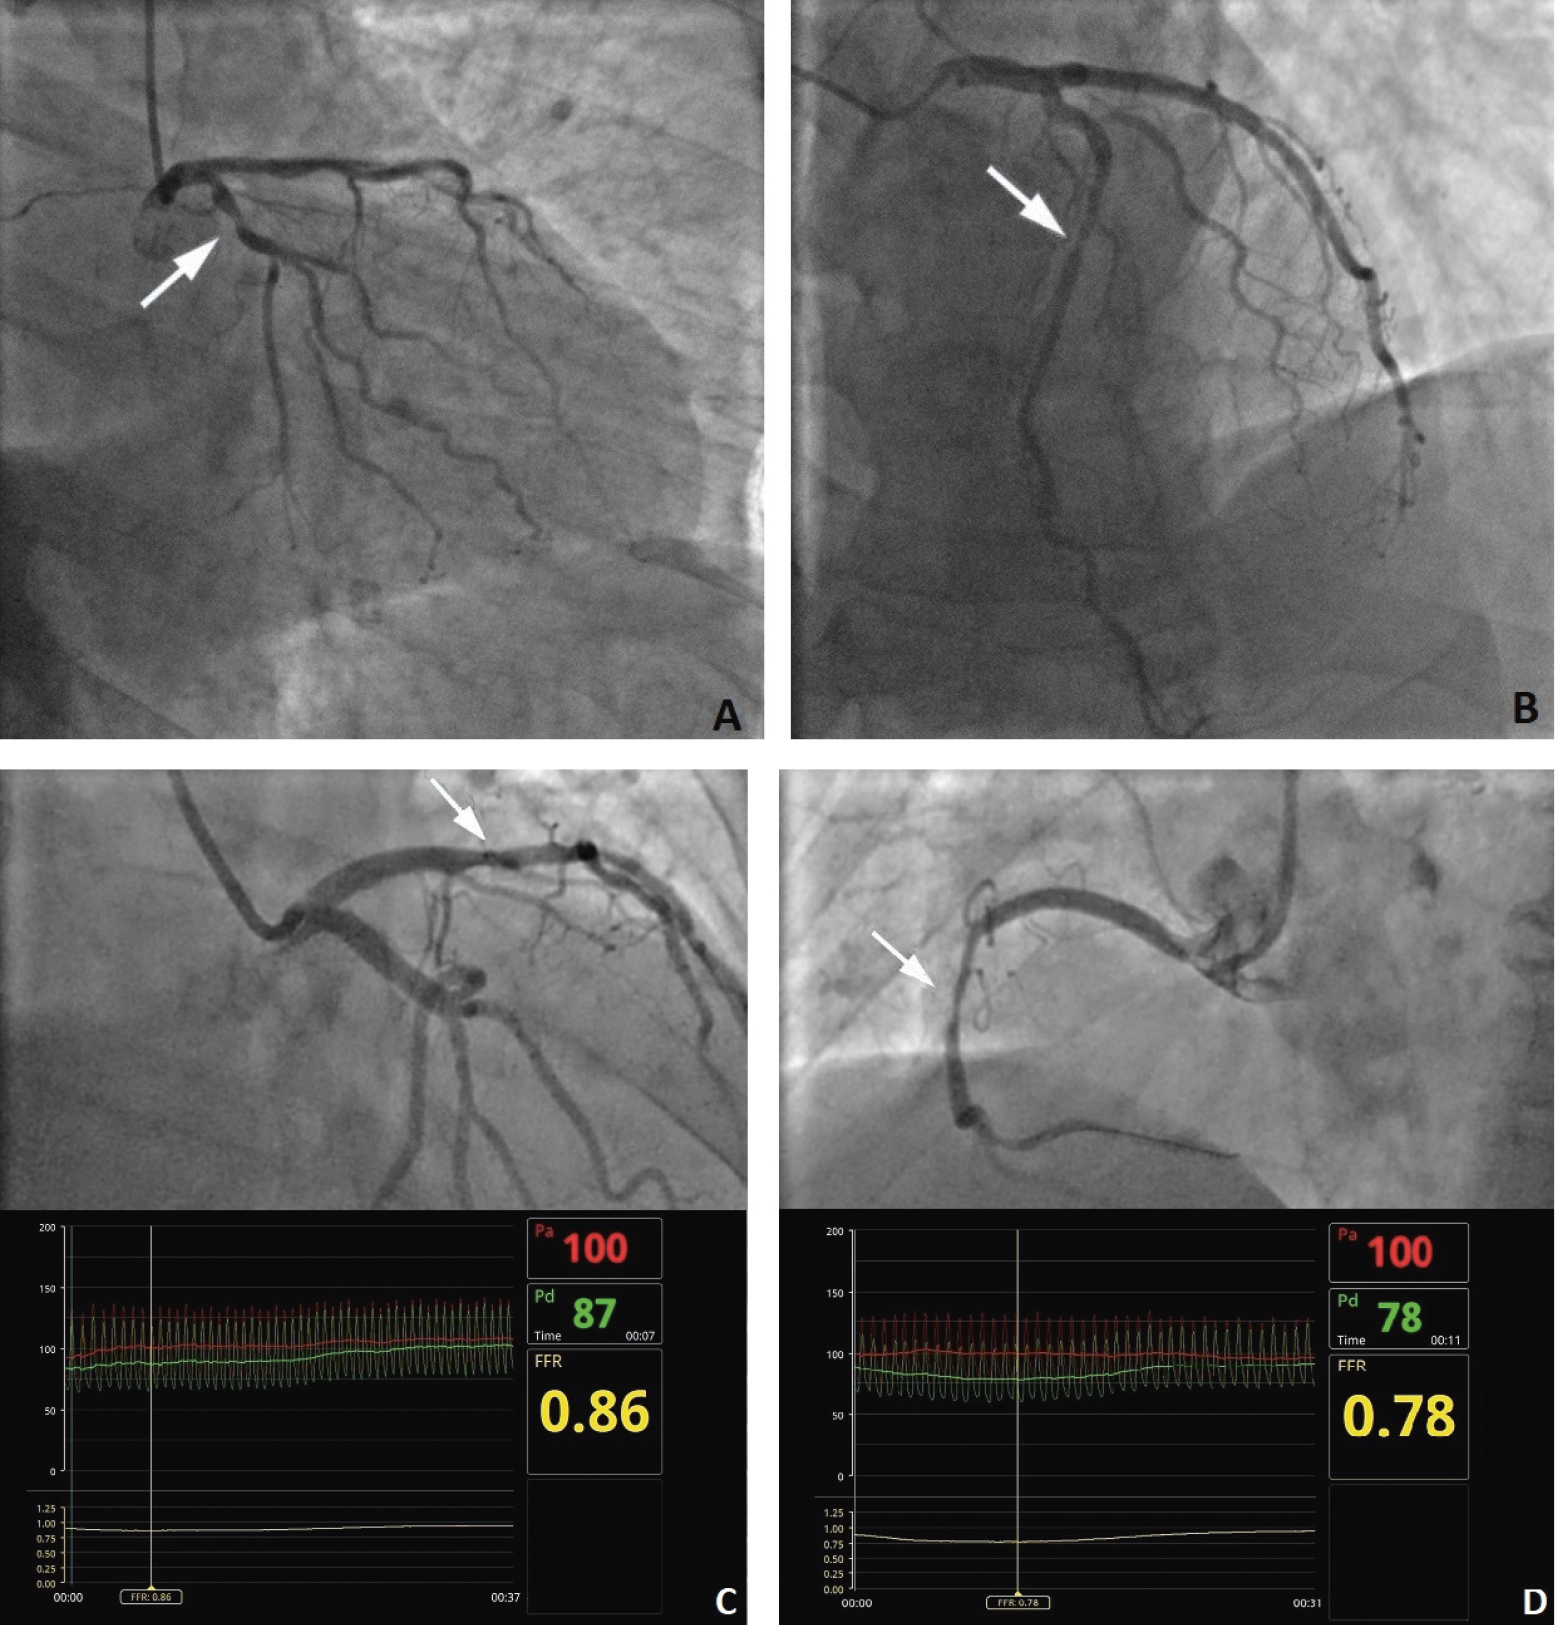

Precise identification of significant stenosis in coronary artery disease (CAD) is of major importance during the treatment and decision-making process. The accuracy of diagnostic procedures enables identification of patients who may benefit from revascularization. In numerous centers, coronary angiography remains the gold standard of diagnostics to select the best therapy, which may include coronary artery bypass grafting (CABG), percutaneous coronary intervention (PCI) or pharmacotherapy.1 Interpretation of stenosis based only on angiography remains challenging due to several limitations, such as contrast streaming, vessel covering, two-dimensional representation of the structures, and difficulties in evaluation of stenosis severity. Previous studies disclosed that intra- and interobserver variability of angiographic interpretation of the presence of significant narrowing ranges from 15% to 45%,2, 3 which presents a risk of unnecessary PCI treatment or inappropriate deferral of revascularization (Figure 1). To improve the decision-making process, current guidelines recommend evaluating coronary pressure-derived fractional flow reserve (FFR) for the hemodynamic assessment of lesions in stable patients.4 As a consequence, FFR has become a valuable modality in catheterization laboratories. Nevertheless, physiological assessment of epicardial coronary stenosis using FFR can also be hampered by its limitations. The FFR is performed in hyperemia to minimize the effects of the coronary microcirculation; thus, it requires the administration of pharmacological agents such as adenosine. Multiple factors such as diabetes, left ventricular hypertrophy and severe aortic valve stenosis can disrupt maximal hyperemia and lead to overestimation of the FFR measurement.5 Furthermore, characteristics of lesions such as bifurcation, left main stem disease, serial lesions, or stenosis in ostium can also affect the FFR evaluation.6